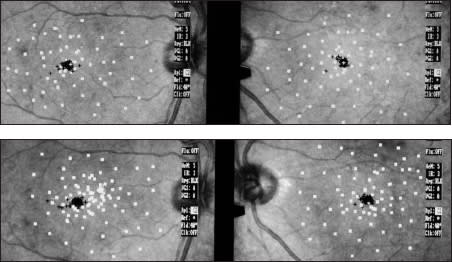

Figure 5. Pretreatment (top) and post-treatment microperimetry with SLO (bottom); right eye underwent treatment.